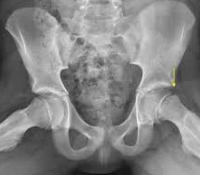

子牛、若牛では四肢の骨折の1/5を占めます。

骨幹の骨折がもっとも多く、螺旋骨折または骨折線の長い斜骨折になり、骨折騎乗がおこります。橈骨神経の損傷が避けられませんが、複雑骨折はまれです。

近位骨端、大結節の骨折も報告されていますが、小動物に発生が多い顆骨折または顆間骨折はほとんど知られていない。

骨幹の完全骨折では、重度の混跛、腫脹、疼痛を呈し、患肢を上にして横臥します。起立すると、患肢を外側方に出し、他動運動では過度の外転、内転および激痛と軋轢音があります。肘が沈下する。

大結節の骨折および骨亀裂では、懸跛と局所の圧痛(肩跛行)を示します。肩関節炎、肘関節炎、フレグモーネ、筋の挫傷との鑑別診断が必要です。